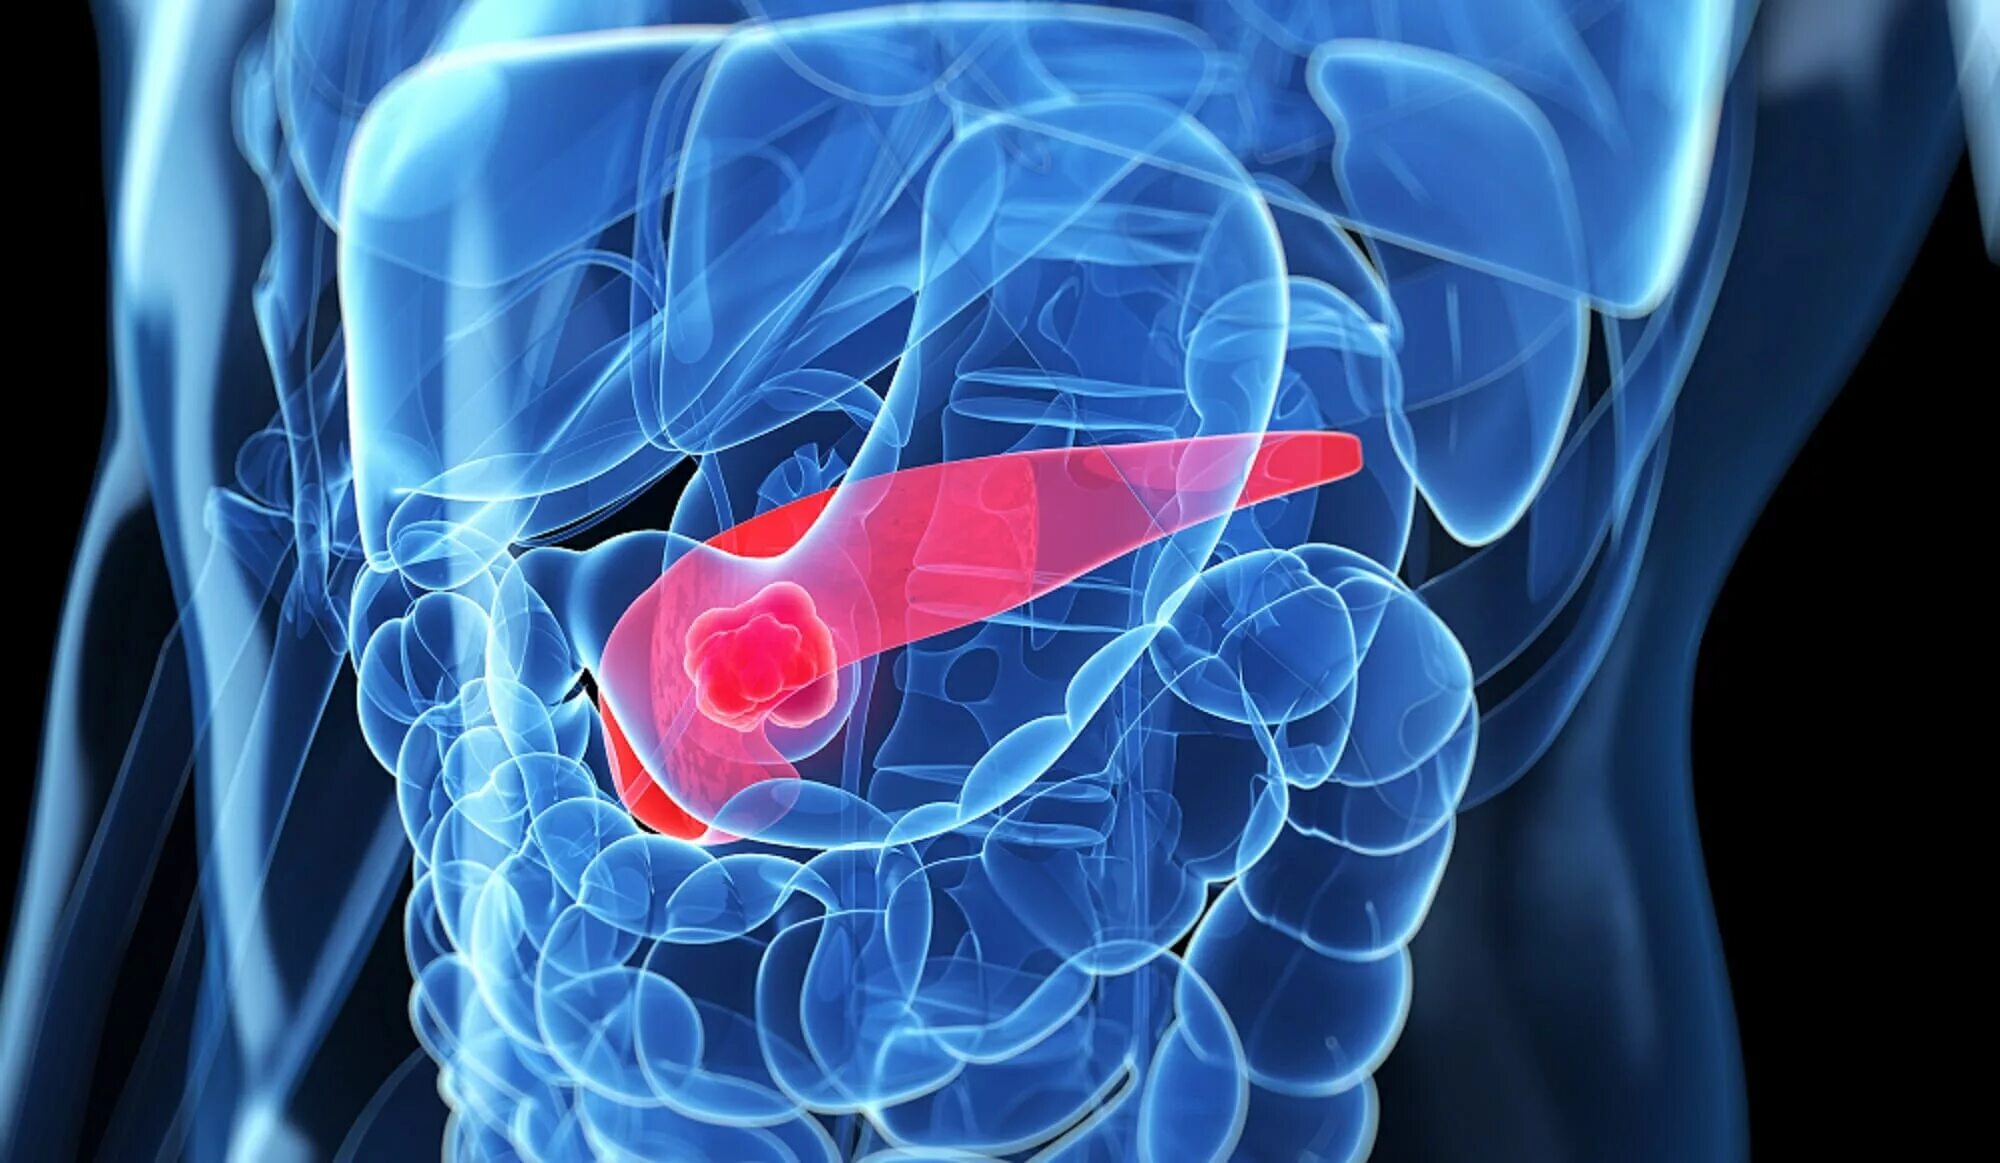

Пересадить поджелудочную железу